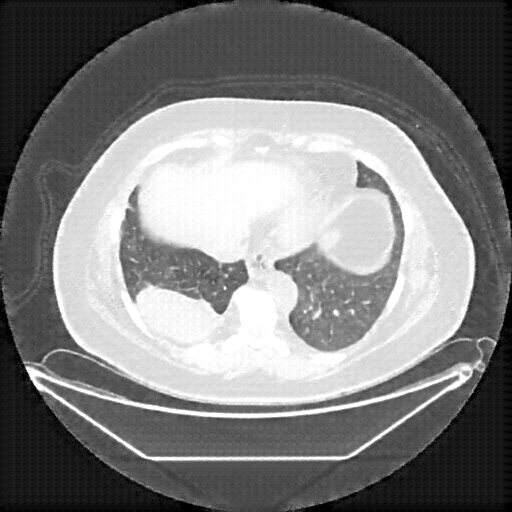

Image Grid

4Γ—3 grid: Rows show different image types (Original NATIVE, Reconstructed NATIVE, Original VENOUS, Generated VENOUS), Columns show windowing techniques (No Window, Lung Window, Mediastinum Window)

Original VENOUS CT scan

No window - Raw intensity values

Mediastinum window (WL 40, WW 400 β†’ Low βˆ’160, High +240)

Generated VENOUS CT scan (A→B translation)